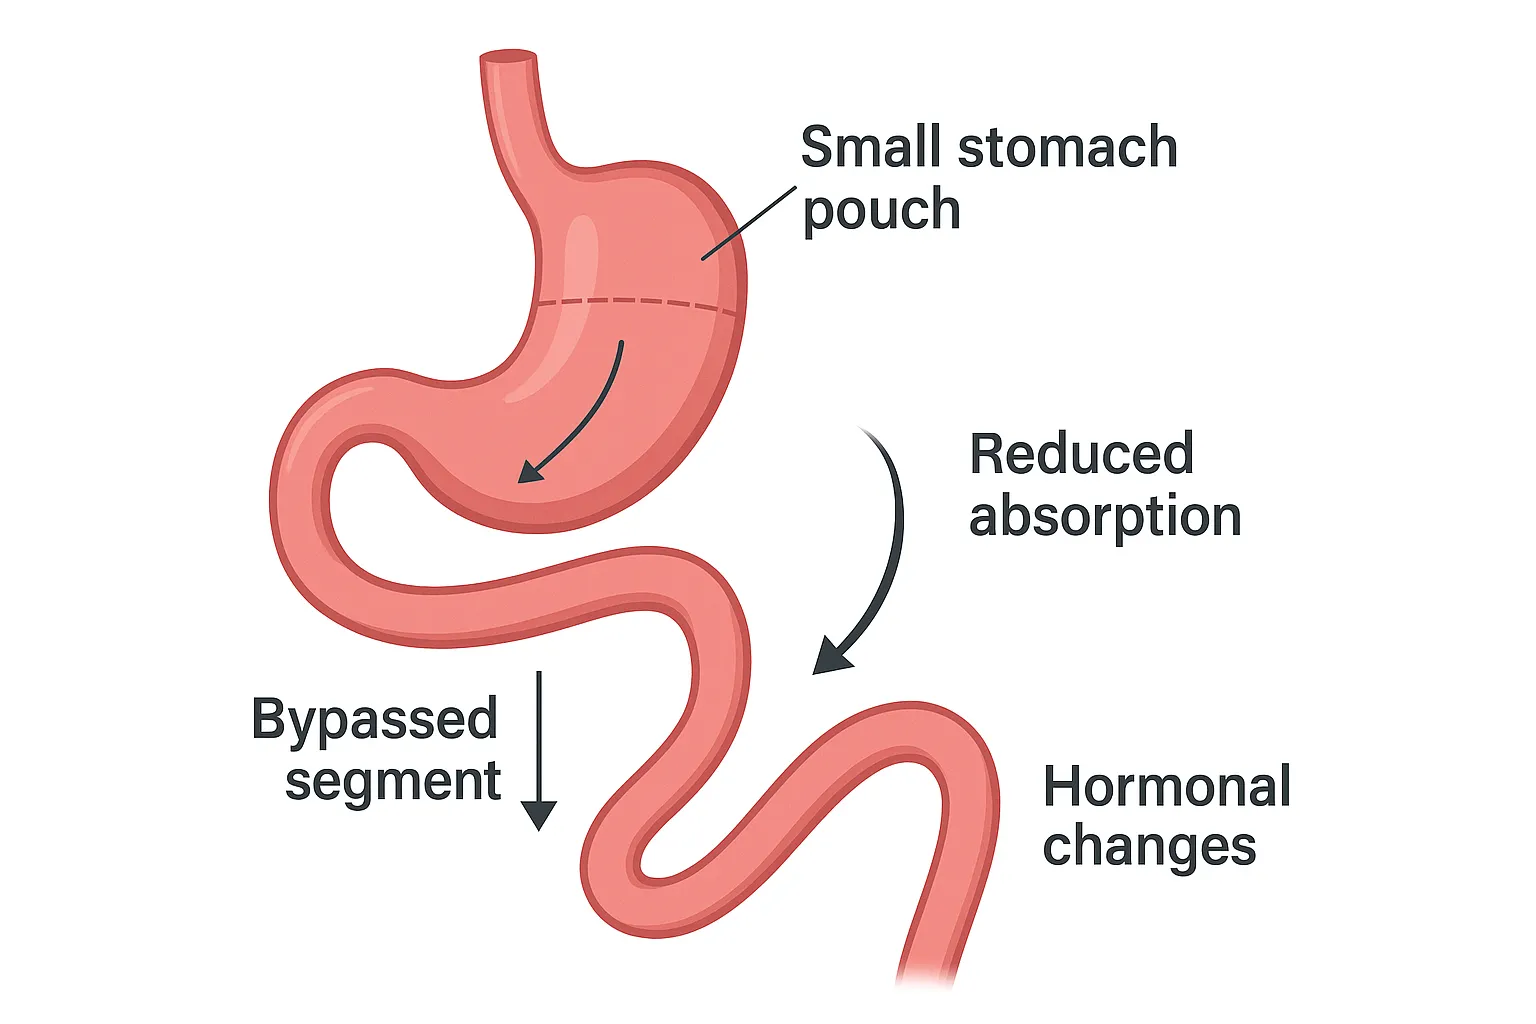

جراحی بایپس معده (Gastric Bypass Surgery یا Roux-en-Y Gastric Bypass) یک روش جراحی پیشرفته لاغری است که شامل دو تغییر اساسی در سیستم گوارشی میشود: اول، ایجاد یک کیسه کوچک از بخش بالایی معده (با حجم حدود ۲۰-۳۰ میلیلیتر) برای محدودیت مصرف غذا؛ دوم، بایپس (دور زدن) بخش باقیمانده معده و قسمت اولیه روده کوچک (دوازدهه و ژژنوم) با اتصال مستقیم کیسه معده به بخش میانی روده کوچک. این مکانیسم نه تنها حجم مصرف غذا را کاهش میدهد، بلکه جذب کالری و مواد مغذی را محدود کرده و تغییرات هورمونی (مانند کاهش گرلین و افزایش GLP-1) ایجاد میکند که اشتها را کنترل و متابولیسم را بهبود میبخشد. عمل بایپس معده به ویژه برای درمان چاقی مفرط (BMI بالای ۴۰) یا چاقی متوسط (BMI بالای ۳۵ با بیماریهای همراه مانند دیابت) مؤثر است و برخلاف روشهای موقتی، نتایج دائمی ارائه میدهد. دکتر محمدرضا مافی، بهترین جراح بایپس معده در تهران، این عمل را با تکنیک لاپاروسکوپی انجام میدهد تا حداقل تهاجم و حداکثر ایمنی را فراهم کند.

جراحی بایپس معده به دلیل ترکیب محدودیت و مالابسوربشن (کاهش جذب)، مزایای منحصربهفردی دارد که آن را به گزینهای ایدهآل برای بیماران با چاقی شدید تبدیل کرده است. کلیدیترین مزایا عبارتند از:

• تغییرات هورمونی مثبت: کاهش هورمون گرسنگی (گرلین) و افزایش هورمونهای سیری، که اشتها را به طور طبیعی کنترل میکند.

4. بایپس روده: بخش اولیه روده کوچک (دوازدهه) بایپس شده و کیسه معده مستقیماً به بخش میانی روده (ژژنوم) متصل میشود، ایجاد یک مسیر Y شکل (Roux-en-Y).